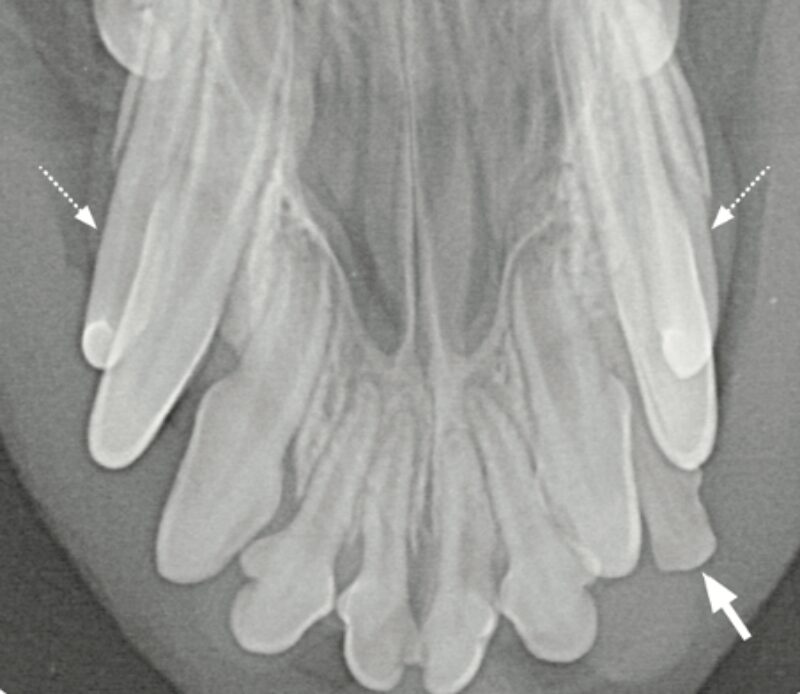

Der Röntgenbefund zeigt den doppelt angelegten I2 im Oberkiefer links sowie eine periapikale Radioluzenz (★) und einen erweiterten Parodontalspalt (▶️). Aufgrund der Überlagerung der Wurzelbereiche wie hier im linken Incisivibereich konnte dieser erst durch die Anfertigung einer intraoralen Schrägaufnahme besser beurteilt werden.

Differentialdiagnostisch sollten persistierende Incisivi – Milchzähne (▶️) ausgeschlossen werden. Sofern stomatologisch wie röntgenologisch keine Hinweise auf eine Zahnerkrankung vorliegen, kann der zusätzliche Zahn belassen werden. Allerdings wird ein Zuchtausschluss empfohlen.